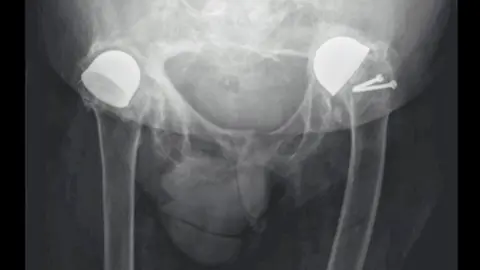

Mr Sharp, a great-grandfather of 14, won a Guinness World Record as his left hip has lasted for nearly 70 years.

PA/Family handoutAlmost a decade later he was informed by the hospital he had been chosen for experimental surgery using a Vitallium cup, and eventually had both hips treated.